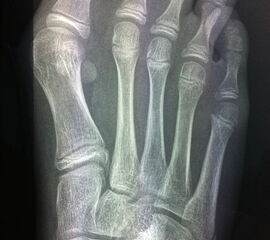

Die Indikation für eine inkomplette DMMO von dorsal Richtung plantar ist der Morbus Köhler II. Hier erfolgt eine dorsal extendierende retrokapitale Osteotomie mit verbleibender plantarer Kortikalis. Ein 1.4 oder 1.6 mm Kirschner-Draht wird in den Schaft von plantar eingeführt und das Köpfchen anschließend über einen Draht in eine verbesserte Gelenkkongruenz gedrückt und darüber gleichzeitig fixiert (Abb. 19).

Abb. 19 a-b: präoperative Diagnostik bei M. Köhler II (a) und postoperativer Verlauf nach minimaler Osteotomie und Köpfchenanhebung mit einem Draht (b).

Zum Lesen der Bildbeschreibung und zur Vollansicht bitte die Bilder anklicken. Bilder: A. Helmers.